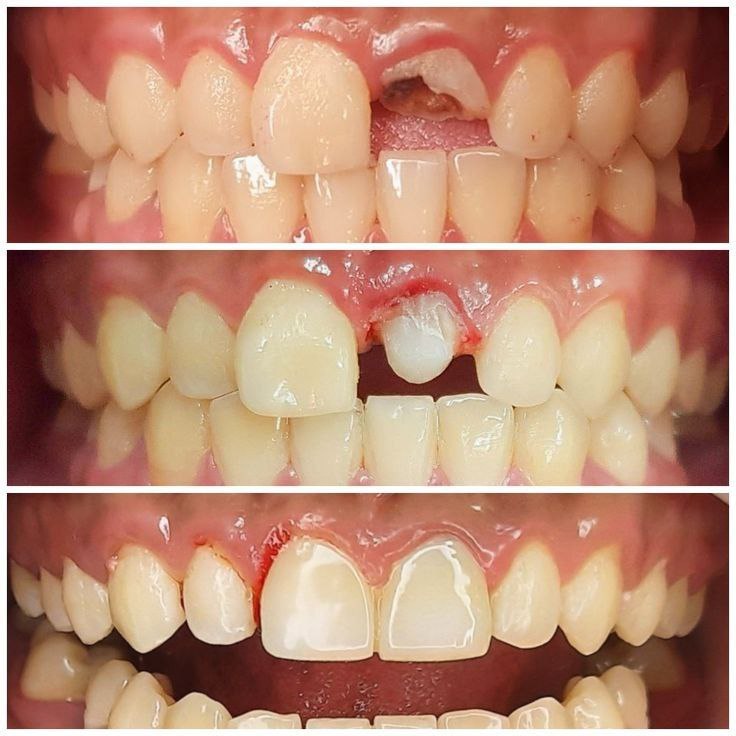

جراحی ریشه شکسته

ترمیم کامپوزیت

پست ریختگی